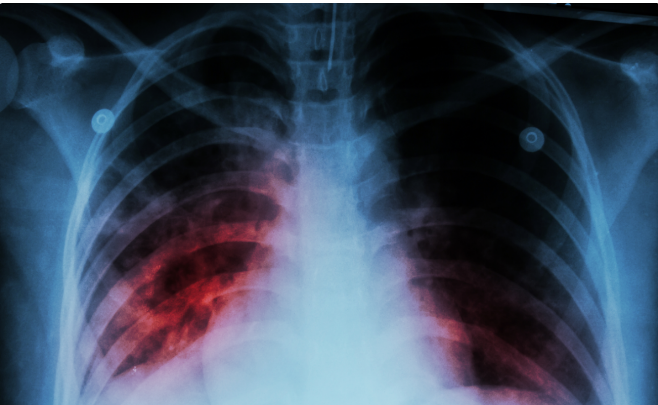

Ötən il 198 uşaq və yeniyetmə vərəm xəstəliyinə yoluxub.

Bunu Səhiyyə Nazirliyi Elmi Tədqiqat Ağciyər Xəstəlikləri İnstitutunun direktoru İradə Axundova deyib.

O bildirib ki, 2024-cü il üçün bu göstərici 278 olub.

"2015-ci ildə hər 100 min nəfərə düşən vərəmlə xəstələnmə göstəricisi 41,1 olduğu halda, 2025-ci ildə bu rəqəm 21,5-ə enib. Vərəm xəstələrinin təxminən üçdə ikisini kişilər, üçdə birini isə qadınlar təşkil edir. Xəstəliyin aşkarlanma səviyyəsi də əhəmiyyətli dərəcədə artıb. Belə ki, 2015-ci ildə bu göstərici 53 faiz olduğu halda, 2025-ci ildə 86 faizə çatıb”, deyə o bildirib.